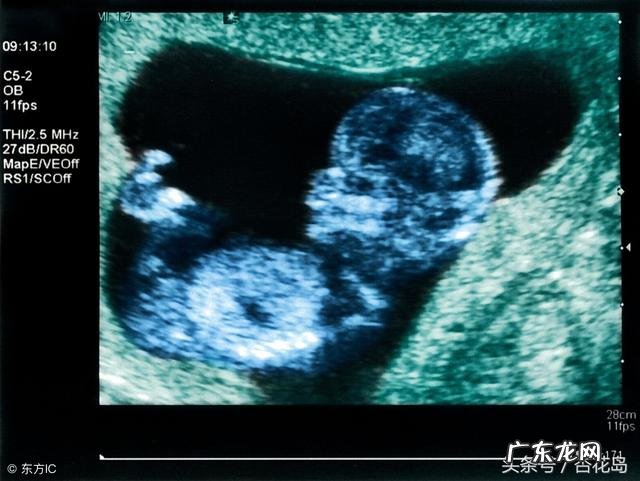

【B超对胎儿有影响么?】按照正规的产检流程,整个孕期应该做5-6次B超,如果孕妇有其他症状,检查次数会相应增加 。有不少孕妇会产生疑问:做这么多次B超不会有辐射吗?会不会影响胎儿健康呢?

一般情况下每次做B超的时间控制在几分钟内是不会对胎儿有影响的 。B超检查的工作原理是利用超声波,不同于X线,它属于无创性检查,利用的是超声波的物理规律如散射、折射等,将信号转换为图像,完成对人体各种器官的探查,是没有辐射性的 。而且在适当的孕周做B超检查,可以确定孕周,观察胎儿的数目、大小、发育情况,对于指导临床有着举足轻重的意义 。

随着健康意识的普及和经济水平的提高,人们对于B 超的接受程度也得到了明显提升 。尽管目前没有研究可以证明超声波对胎儿有致畸作用,但是也不用每次产检之前都做,应该在相应的孕周检查就可以:①在确定妊娠后做B超,确定是否是宫内妊娠,根据妊囊大小和头臀径确定孕周 。②在12-13周做一次B超,查NT值,可以早期筛选染色体异常 。③孕14-20周期间做唐氏筛查前需要做一次B超,看双顶径是否处于3.0-4.9之间,判断是否可以进行唐筛检查 。④在孕中期22-24周做四维彩超排除一些基本的畸形 。⑤孕晚期38周和40周时各做一次,判断胎儿大小及羊水多少,根据胎位判断分娩方式 。⑥如果40周后还未发动分娩,那么一周需要做1-2次B超 。当然,如果在怀孕期间出现了腹痛、阴道出血、胎动胎心异常都需要及时复查B超,观察胎儿情况,评估胎儿是否健康 。